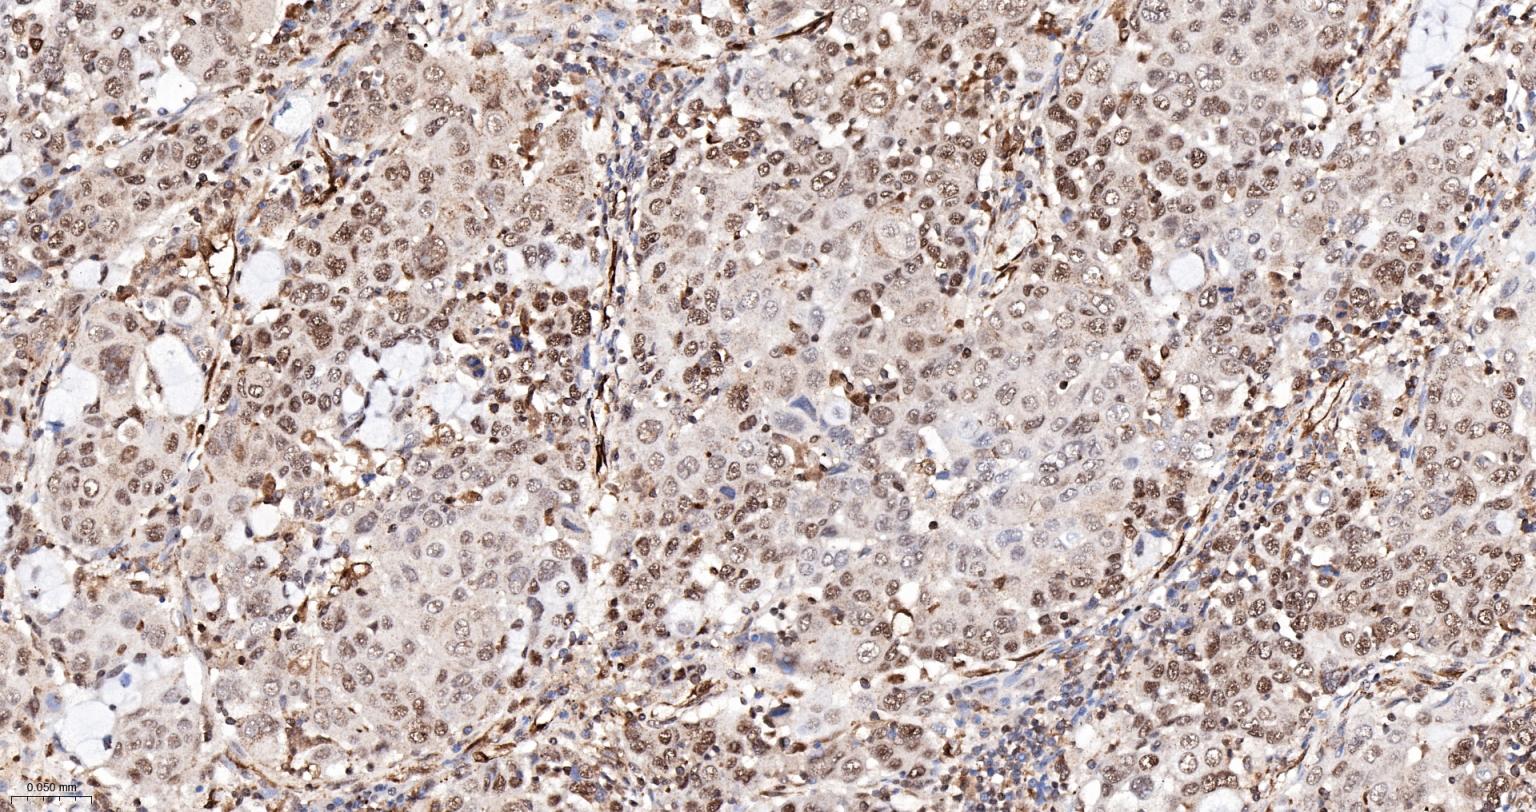

Paraformaldehyde-fixed, paraffin embedded Human Liver Cancer; Antigen retrieval by boiling in sodium citrate buffer (pH6.0) for 15 min; The section was incubated with PRPF19 Monoclonal Antibody, Unconjugated (bsm-61268R) at 1:200 overnight at 4°C, followed by conjugation to the bs-0295G-HRP and DAB (C-0010) staining.